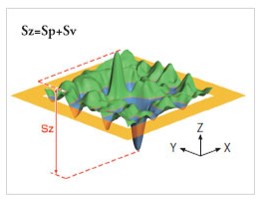

You can also perform 3D acquisitions of the skin surface. Thanks to a technique called stereo photometric, the C-Cube analyses several images under different lighting conditions. The software estimates surface normals. Combined with geometric calibration, it produces elevation information at every pixel.

Thanks to its unique ability to measure 3D parameters, it is possible to measure button elevation in terms of peak height (Sp) and total amplitude (Sz), proving that the product under test has an effect if the peak elevation decreases over time.

Pimple elevation Peak height and amplitude